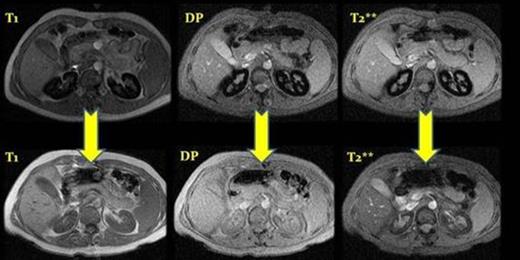

MRI before and after eculizumab treatment, case number 2. ( T1, DP and T2**) After a year of treatment we observed a depletion of iron deposits in the renal cortex.

At diagnosis the median hemoglobin of the 7 patients was 8.9 g/dl (8.2-12-4), the PNH median PNH clone size was 77% (60-90) and the median LDH level was 2340 U/L (1100-3600). Three patients presented an important accumulation of iron in the renal cortex, with much lower signal intensity than the medulla in the T2-weighted MR images. One patient with mild hemolysis (Hb 12.4 g/dl, 20% reticulocytes and 1,100 LDH) did not present iron accumulation in the renal cortex, and neither did the 2 patients studied after 2 a 3 years of eculizumab treatment. All the patients improved, presenting median of Hb of 11,2 g/dl ( 9,5-12,9) and of LDH of 520 U/L ( 430- 721). The patient studied after 8 months showed an increase of iron in the renal cortex that persisted, despite the improvement with the treatment with eculizumab, with increase of the Hb and decrease of the LDH levels; this patients had a C hepatitis and positivity on the hemochromatosis genes C282Y/H63D, with important iron hepatic overload (11-17 mgFe/g). In the rest of the patients the hepatic iron was normal, with values from 0.5 to 2 mgFe/g, except in one case where the levels were higher (10 mgFe/g) due to previous transfusions used to treat an aplastic anemia pre-PNH. Myocardial iron was normal in the 7 patients, with values ranging from 33 to 60 ms in T2. Only one of the patients presented several episodes of acute renal insufficiency, related with hemolytic crisis, with residual proteinuria, that disappeared when treated with eculizumab.